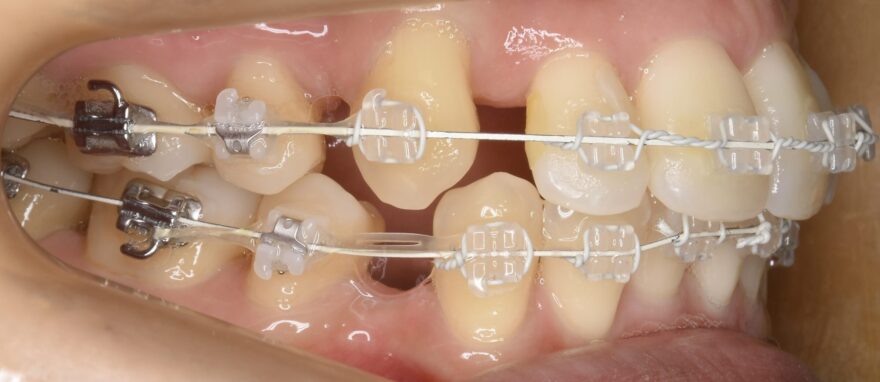

治療中の口腔内写真

上下ともには表側に矯正装置が付いています。

金属ワイヤーの外側にのみ白いコーティングがされていることが分かります。